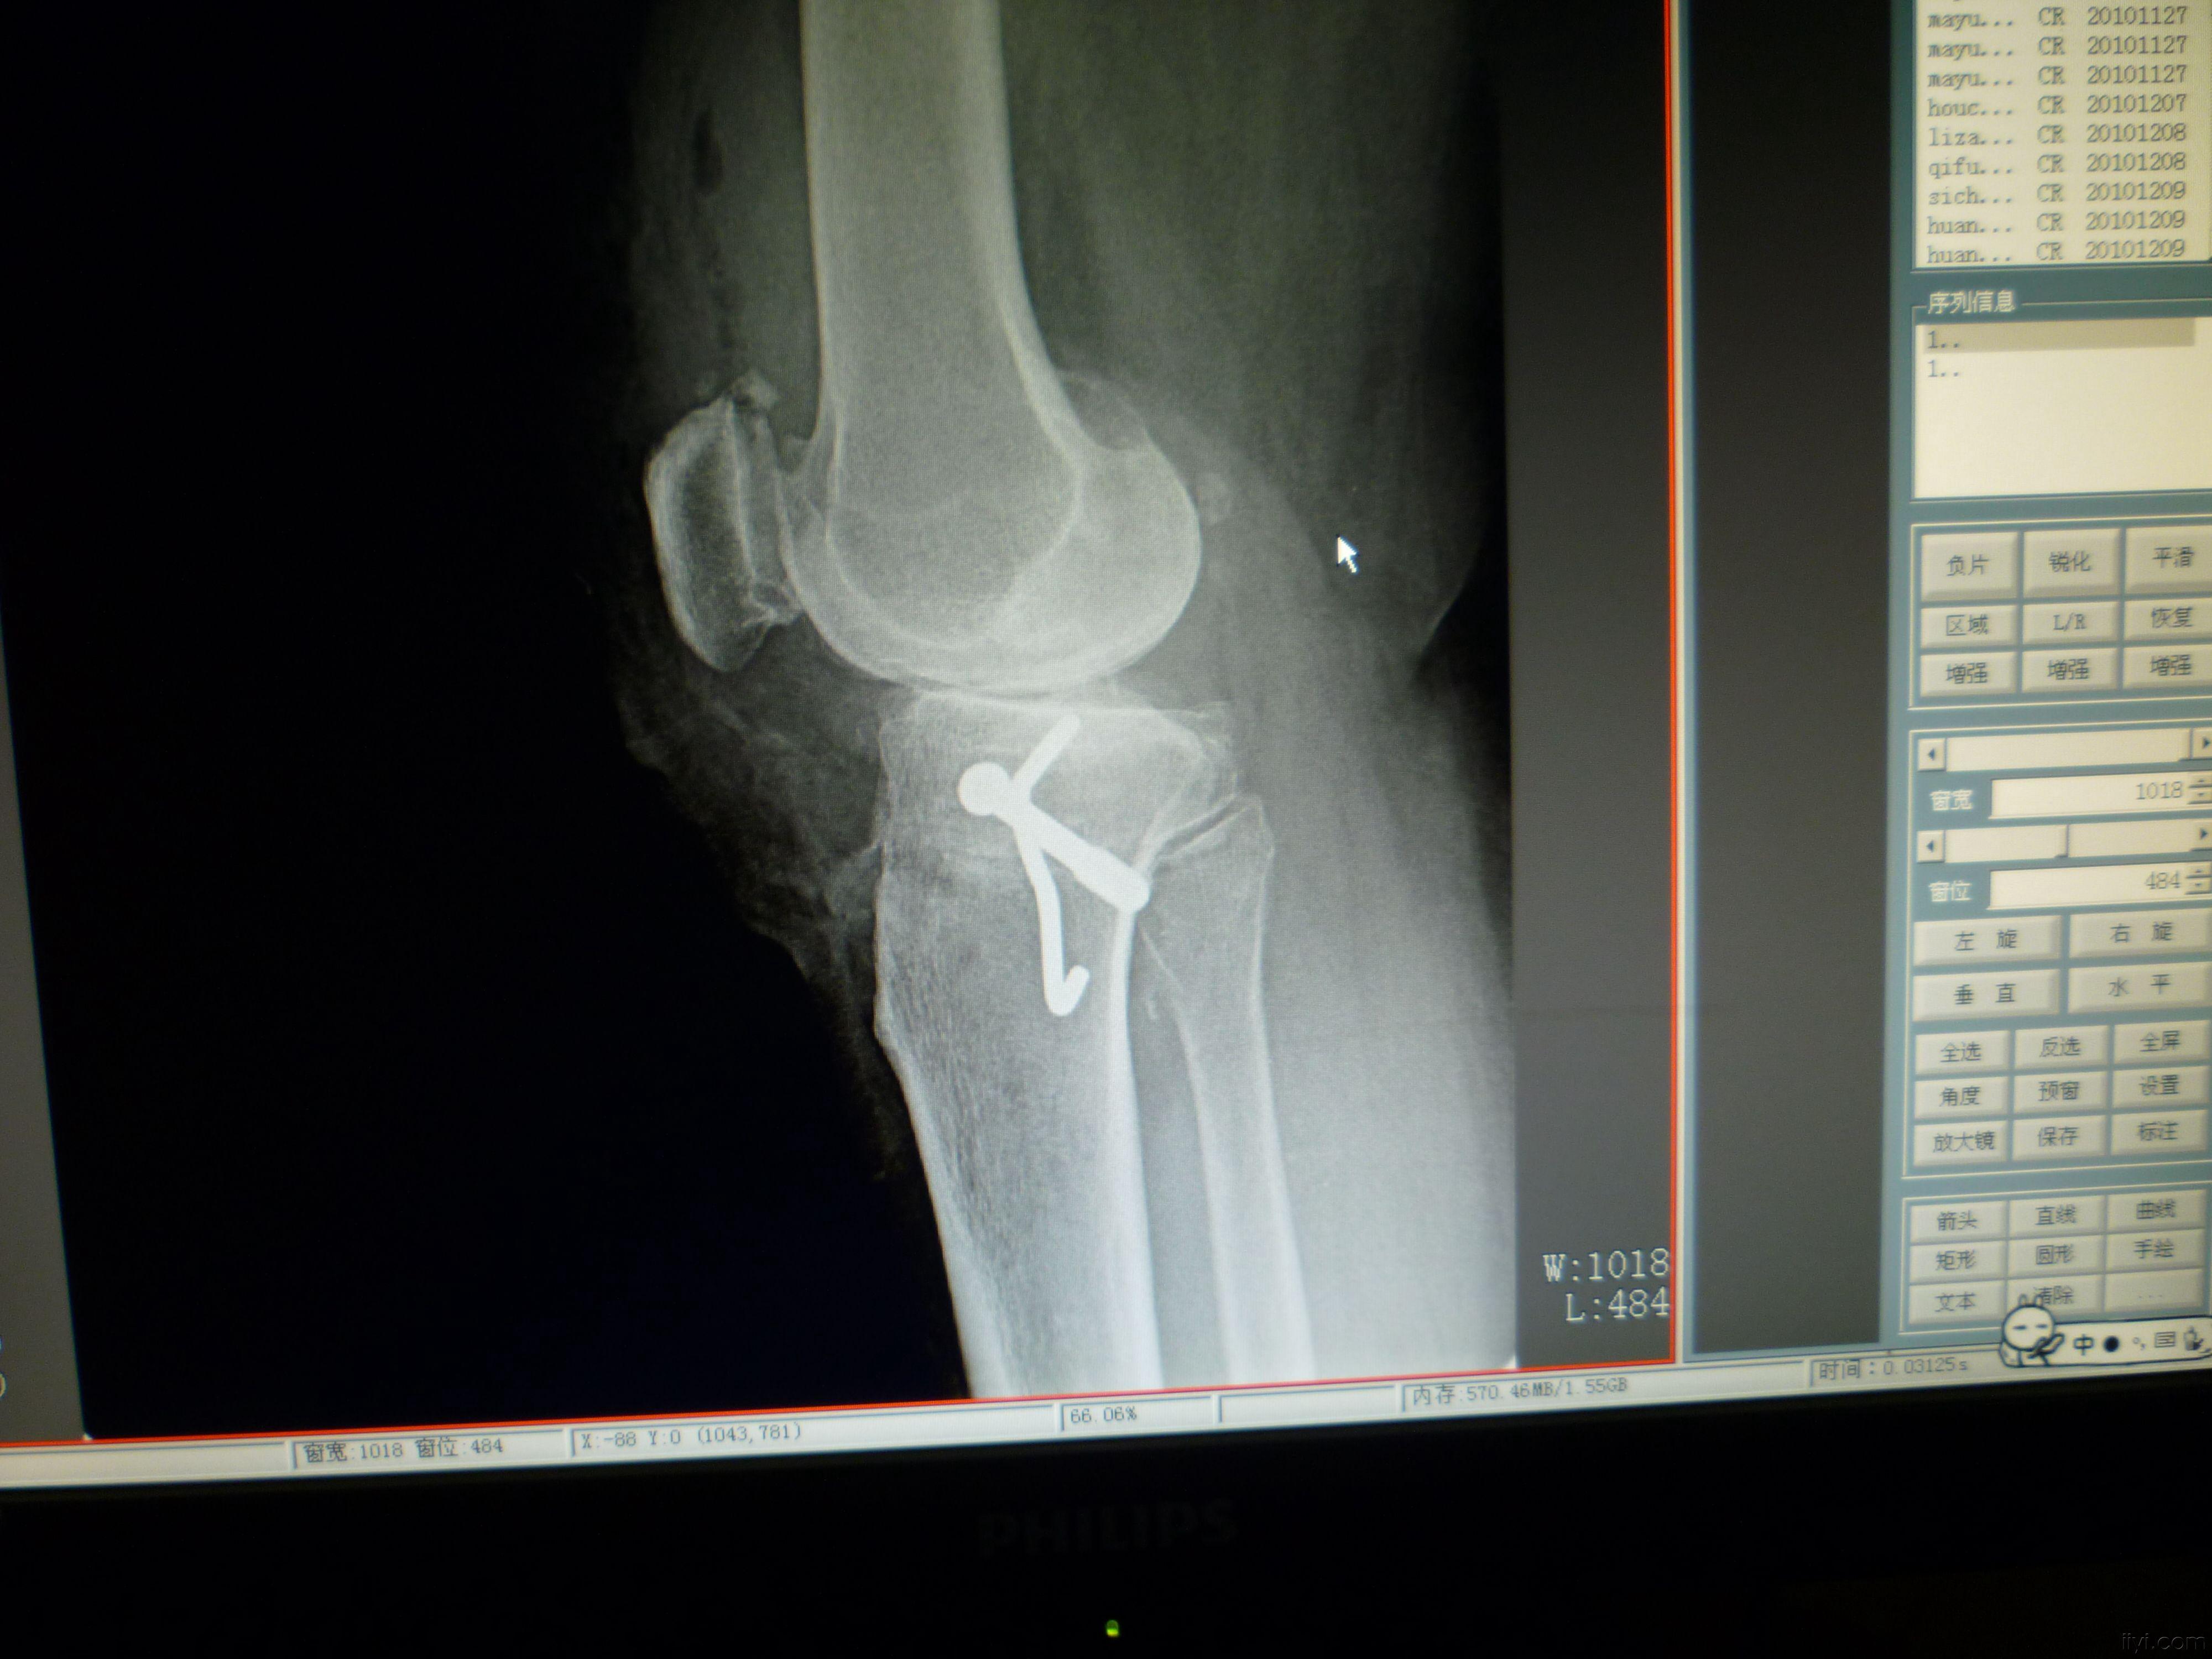

膝关节退行性变膝内翻矫形骑缝钉内固定

图片尺寸4000x3000

u型螺钉(骑缝钉) - 上海康定医疗器械有限公司

图片尺寸800x800